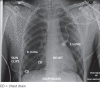

Surgical repair of pulmonary vein injury from blunt trauma

Pulmonary vein deceleration injury is rare and patients can be deceptively stable for a period after injury. Quick diagnosis and transfer to the operating theatre is the only way to treat this potentially lethal injury successfully. Techniques of repair are a useful addition to the cardiovascular surgeon's repertoire.